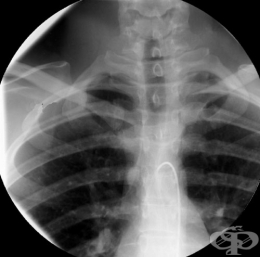

Шийно ребро - изображениеПо време на ембрионалното развитие на гръбначния стълб се оформят 29 чифта ребра, от които 12 чифта оформят гръдния кош, а останалите претърпяват обратно развитие. Ð’ шийния дял тази редукция започва отгоре – надолу, и ако не настъпи докрай в долния сегмент на шийния дял, се оформят един или два чифта добавъчни ребра.

Палпаторно може да се опипа шийно ребро като костно възвишение в супраклавикуларната ямка.  Рентгенографично се вижда шийното ребро най-често едностранно или двустранно.